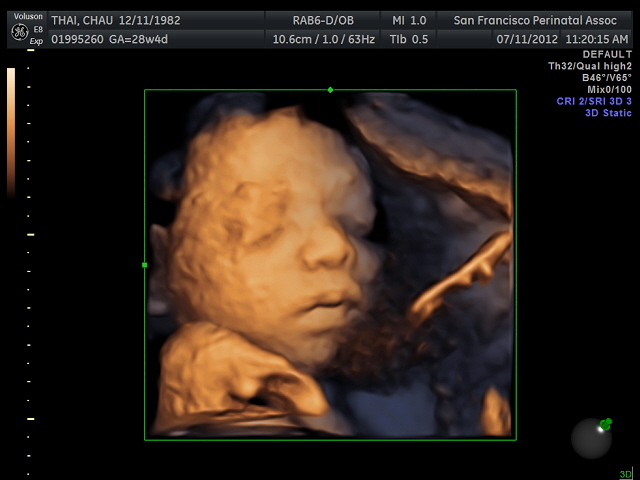

Fetus With A Cleft Lip At 28 Weeks Gestation Three Dimensional

Clp 3d Twin Ultrasound Zander 28 Weeks